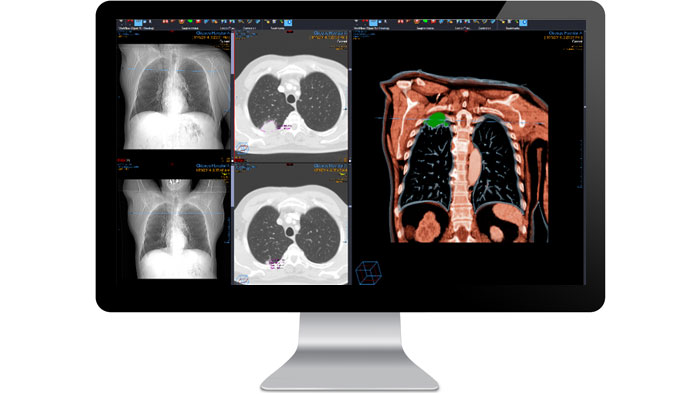

Radiología

Aporte valor a los servicios que ofrece y sitúe la radiología como una disciplina esencial. Nuestro módulo de radiología aumenta la productividad a la vez que le permite entregar informes con diagnósticos fiables dentro de un contexto clínico.

Potente

Ofrece a los oncólogos los datos de gestión de lesiones que necesitan para planificar el tratamiento.

Avanzado

Los conjuntos de herramientas clínicas ampliados y la creación de informes multimedia permiten mediciones más precisas, el aumento de la productividad y la obtención de más información clínica.

Flexible

Facilita la incorporación de funciones de telerradiología para ofrecer informes de calidad a los hospitales sin posibilidad de realizar lecturas.

Funciones y ventajas

Flujo de trabajo de medición de oncología

Proporcionar información clínica a los especialistas es crucial, sobre todo en campos como la oncología. La aplicación Lesion Management Tool permite ofrecer seguimiento en exámenes de alto valor que requieren una planificación del tratamiento compleja, como es el caso de los exámenes oncológicos. Lesion Management Tool proporciona a los oncólogos los datos necesarios: análisis de tendencias, mediciones y marcado anatómico, entre otros.

PowerViewer

Interpretación de velocidad con reconstrucción multiplanar, representación vascular y reproducción de volumen en solo un clic. PowerViewer volumétrico mejora la vista bidimensional tradicional y crea un único estudio virtual con registro volumétrico de todos los estudios relevantes en 3D en tiempo real, incluidos los exámenes previos, con vistas sincronizadas entre varios conjuntos de datos.

Imágenes avanzadas 3D

Cree, modifique y vea imágenes 3D sin dejar los datos fuente. Vue PACS 3D Imaging gestiona de forma eficaz grandes conjuntos de datos y ofrece una gran velocidad y simplicidad a la hora de mostrar estudios actuales y anteriores en paralelo y aplicar herramientas 3D a ambos. Las opciones de análisis 3D incluyen la proyección de máxima intensidad (MIP), la reproducción de volúmenes y la definición de tejidos. Las imágenes reproducidas en 2D y 3D se cargan automáticamente para proporcionar un resumen de la anatomía completa, con posicionamiento automático en 3D de las líneas de referencia cruzada.